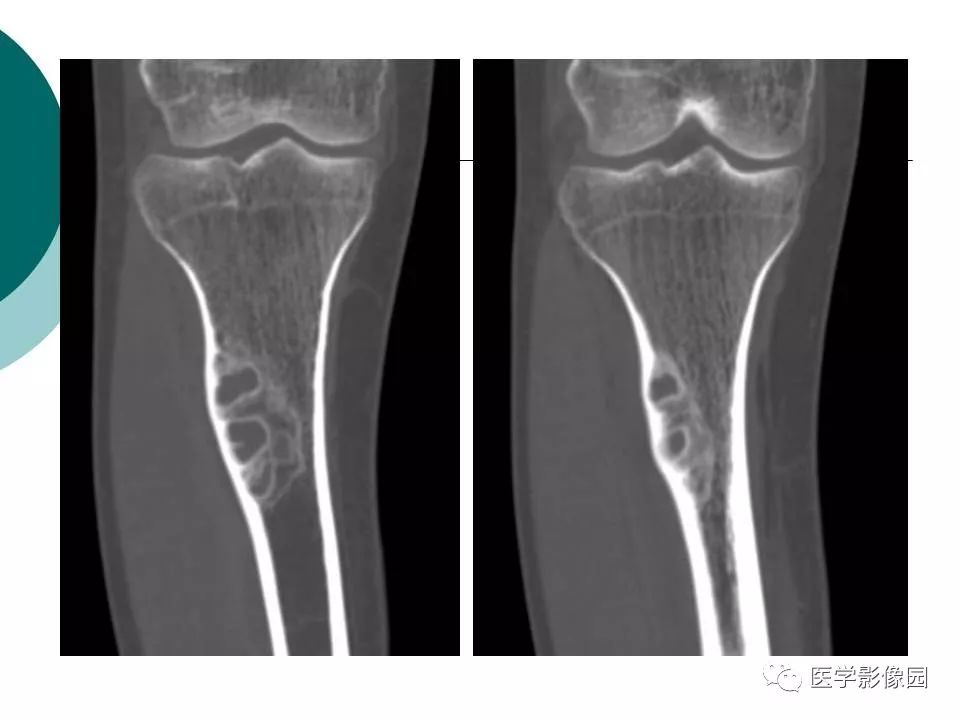

【病例】胫骨非骨化性纤维瘤1例CT及MR